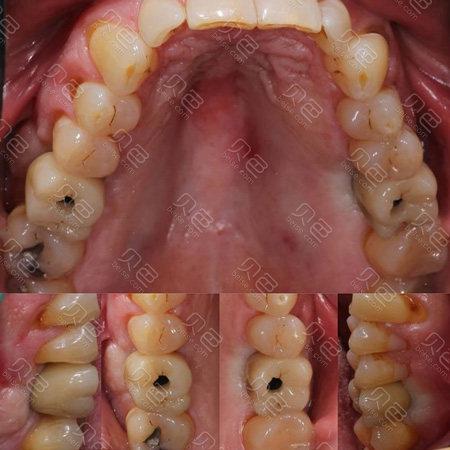

(图片来源网络,侵删)

🩺 牙冠高度不够会带来什么问题?

- 美观问题: 尤其在前牙区,牙冠高度不足会让牙齿显得短小、不自然,影响笑容美观,与邻牙高度不一致也很明显。